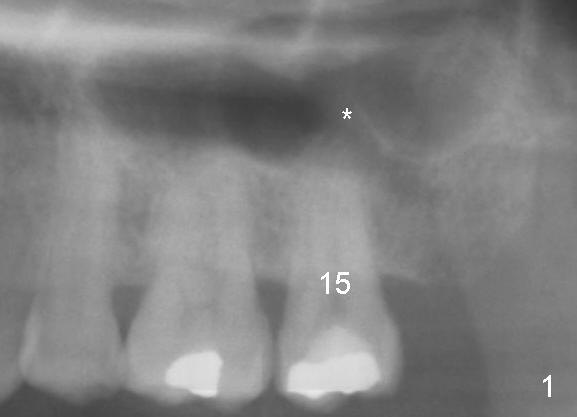

A 52-year-old black man fails to return to finish root canal therapy for the tooth #15; ultimately it is non-salvageable (Fig.1-3).  The tooth has 3 basically fused roots (Fig.4 black (buccal) and red (palatal) outlines), above which is the sinus septum (*).  By inserting an immediate implant into the sinus septum, primary stability should be high (Fig.5 vs. 6).